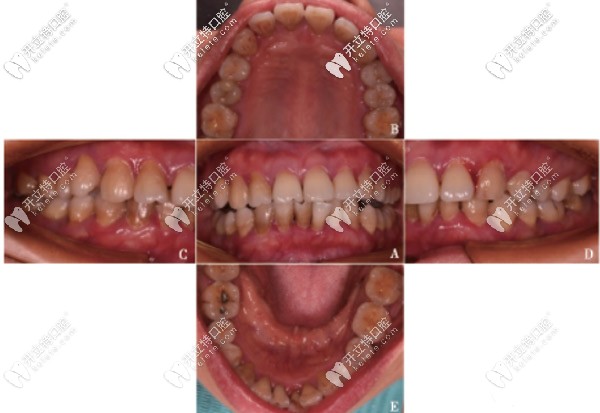

重度牙周炎案例:除了控制菌斑外還可聯(lián)合引導(dǎo)性組織再生術(shù)

顧客44歲被評(píng)估為高風(fēng)險(xiǎn)牙周病,屬于重度牙周病范疇。經(jīng)過2年的控制菌斑聯(lián)合引導(dǎo)性組織再生術(shù),已可維持整個(gè)牙周系統(tǒng)的健康與穩(wěn)定。